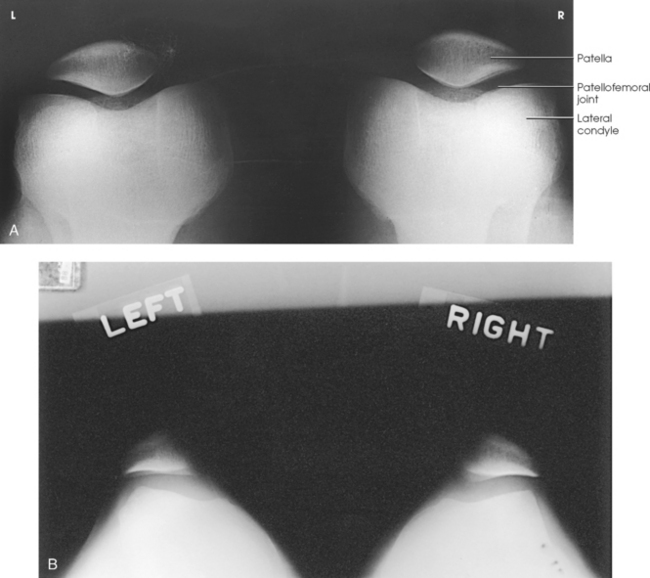

Structures shown: The bilateral tangential image shows an axial projection of the patellae and patellofemoral joints (Fig. 6-156). Because of the right-angle alignment of the IR and central ray, the patellae are seen as nondistorted, albeit slightly magnified, images.

Fig. 6-156 A, Normal tangential radiograph of congruent patellofemoral joints, showing patellae to be well centered with normal trabecular pattern. B, Abnormal tangential radiograph showing abnormally shallow intercondylar sulci, misshapen and laterally subluxated patellae, and incongruent patellofemoral joints (left worse than right). (Courtesy Alan J. Merchant.)